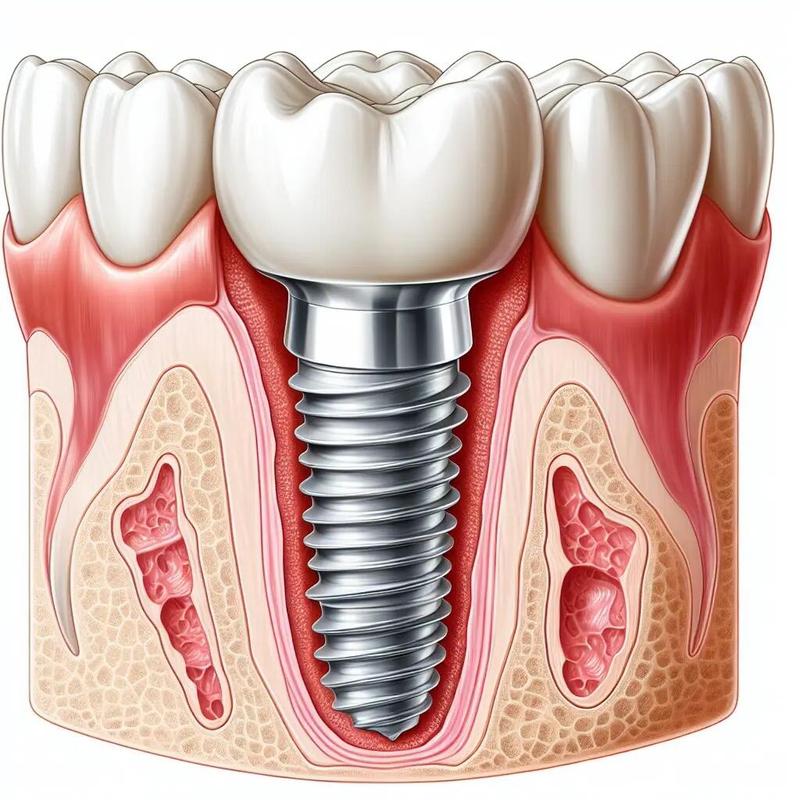

(图片来源网络,侵删)- 数字化种植:通过CBCT扫描和3D导板设计,实现种植位点、角度、深度的精准控制,创伤小、恢复快;